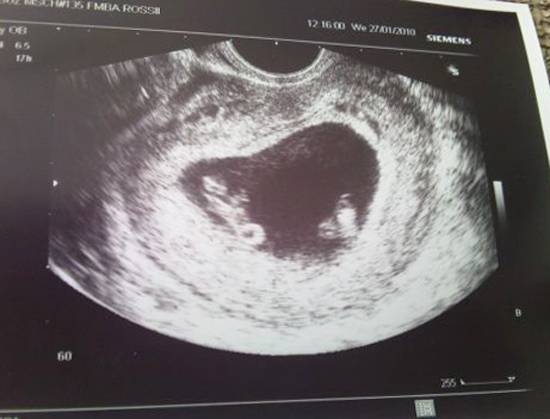

Однояйцевые близнецы на УЗИ